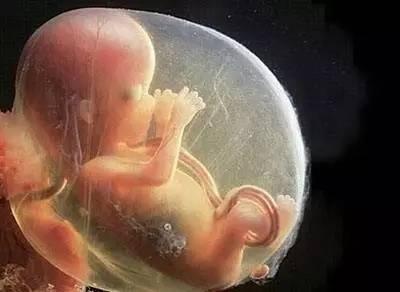

据美国的一项调查表明,每天浓妆艳抹的孕妈妈们胎儿畸形的发生率是不涂浓妆孕妈妈的1.25倍。而对胎儿畸形发育所产生不良影响的主要是化妆品中所含的:砷、铅、汞等有毒物质,这些物质被孕妇的皮肤和黏膜吸收后,可透过血胎屏障,进入胎儿血循环,影响胎儿的正常发育。